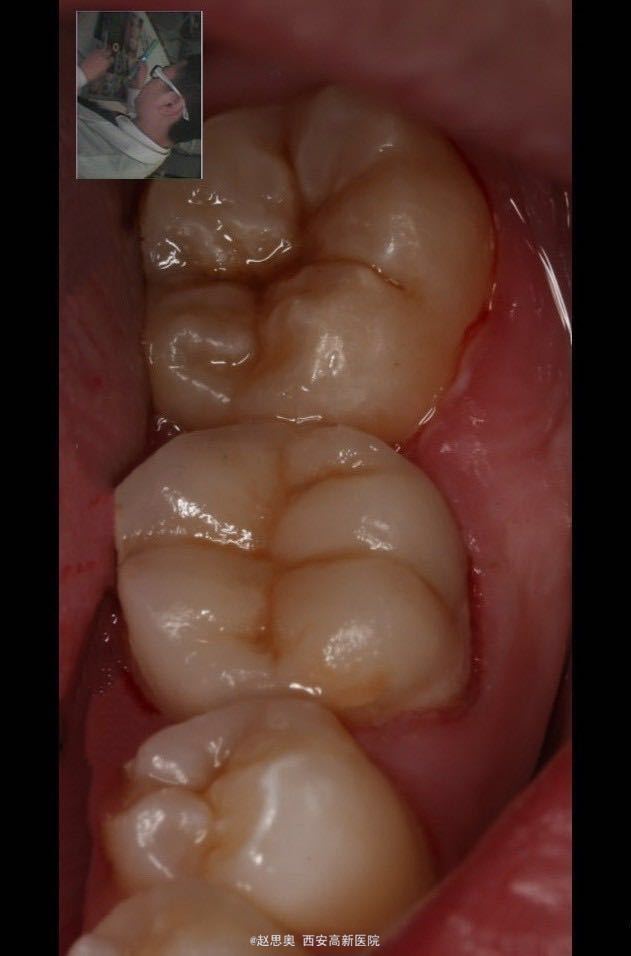

诊断为不可复性牙髓炎,慢性根尖周炎 处理,根管治疗后间接树脂修复

自我评价:感觉窝沟走形不好,窝沟深度不协调,牙尖分布不够好。预后情况和患者交代清楚,告知 术后隐患,定期复诊。 术后思考:意见1、用单反相机拍摄口内同名牙及邻牙照片,堆塑时放大照片用以参考窝沟走形及牙尖斜度 弧度。